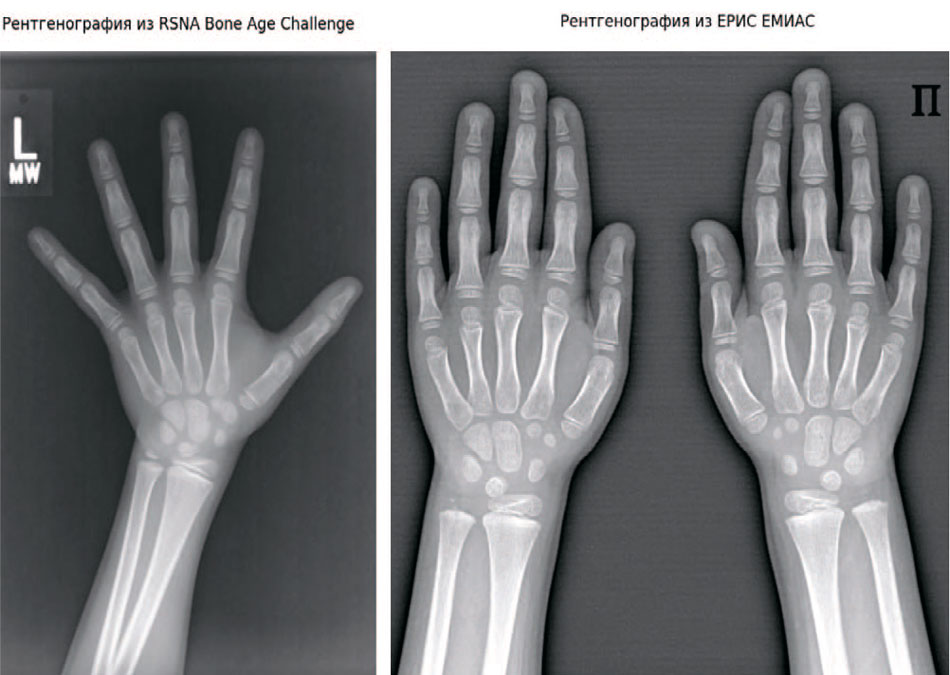

Рис. 2. Методологиями проведения рентгенографии кисти в РФ и США

Fig. 2. Methodologies for performing hand radiography in the Russian Federation and the USA

- ЕРИС ЕМИАС (РФ, Москва). Для дообучения и независимого тестирования (валидации) использовано 200 рентгенограмм высокого разрешения из Единой радиологической информационной системы города Москвы. Эти данные критически важны для проверки устойчивости модели к качеству изображений отечественного рентгеновского оборудования и особенностям укладки, принятым в РФ.

К ограничениям исследования можно отнести использование преимущественно данных датасета RSNA (популяция США) на этапе предварительного обучения. Несмотря на дообучение на российских данных, существуют антропометрические различия между популяциями. Дальнейшие шаги предполагают расширение отечественной выборки для калибровки модели, а также проведение проспективных клинических испытаний для оценки влияния использования ИИ на тактику ведения пациентов.